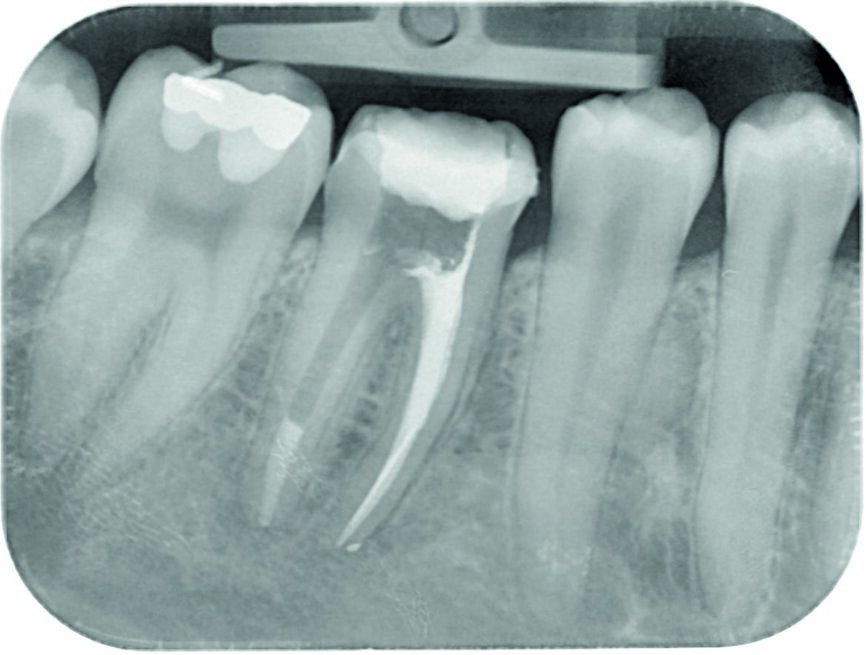

A 34-year-old female patient was referred for endodontic treatment of tooth #46 because of a separated endodontic instrument in the mesial root, which was observed on the initial radiograph (Fig. 1). The patient’s chief complaint was mild pain in the mandibular right posterior region during chewing. She gave a history of a root canal therapy on the same tooth four years earlier. There was no other relevant medical history.

Based on the clinical and radiographic findings, root canal therapy was initiated. A rubber dam was placed and the tooth was accessed without the need for an aesthesia. Crown-down preparation was performed for orthograde endodontic treatment. The mesiobuccal canal was negotiated with a size 0.06 C-file and the separated instrument was removed under magnification with a dental operating microscope (16 ×, Zeiss), and a control radiograph was taken (Fig. 2). The root canals were cleaned and shaped with ProTaper rotary instruments (Dentsply Maillefer). The mesial canals were prepared up to F3. All of the canals were irrigated with a copious amount of 5.25% sodium hypochlorite and 17% EDTA. This was followed by irrigation with 0.9% saline to remove any remnants of hypochlorite and EDTA. Haemorrhage and exudate from the apical region of the distal canal were observed during the instrumentation, which suggested resorption exteriorisation. The canals were dried with absorbent paper points, and calcium hydroxide paste (ApexCal, Ivoclar Vivadent) was placed in the canals as an intracanal medicament, followed by temporary restoration with glass ionomer cement.

Fig. 1: Initial radiographic status of tooth #46

Fig. 2: Control radiograph to assess the removal of a separated lentulo